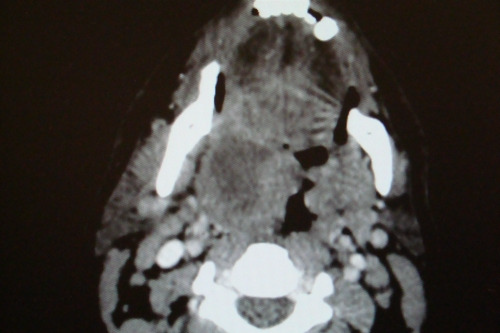

INSTRUÇÃO: Analise a imagem a seguir para responder à questão 07:

Paciente masculino, 20 anos, dá entrada no pronto-socorro, relatando odinofagia unilateral intensa, com irradiação para orelha ipsilateral, febre 39 graus, limitação à abertura bucal, voz anasalada, mas eupneico, estado geral preservado, pulsos cheios e simétricos, normotenso. Quadro com cinco dias de evolução e está em D4 de amoxicilina. Apresenta a tomografia acima.

Sobre esse relato, podemos afirmar: